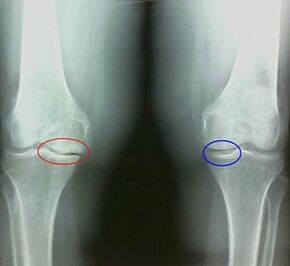

For example, what is the difference between arthritis and arthrosis of the knee joint?With arthritis, the synovial shell of joint tissues occurs.This causes an increase in joint temperature.

Articular waves, a persistent pain syndrome develops, intensifying during movement.With arthrosis, pain occurs only after physical activity, you can hear a characteristic crushing or joint clicks, gradually the joint is deformed and loses mobility.